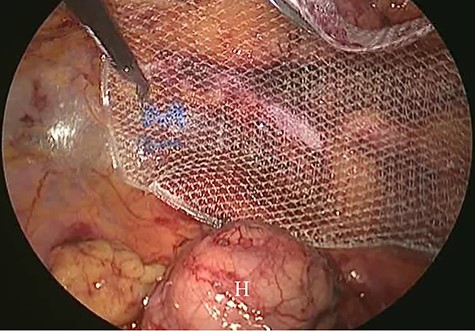

A 62-year-old woman visited our hospital with a 1-day history of lower abdominal pain and bulging from a right groin lesion. Her physical examination showed a right inguinal bulge and pain. Her abdomen was not distended and was without rebound tenderness and muscular defense. However, the bulge in the right groin lesion could not be reduced manually. Contrast-enhanced computed tomography showed a hypodense rounded lesion medial to the right femoral vessels (Fig. 1A) with fluid collection (Fig. 1B), with no intestinal obstruction or ischemia. Based on these physical and radiological findings, the patient was diagnosed as having a right incarcerated femoral hernia containing fat tissue. As there were no clear findings of intestinal obstruction, elective TEP repair was performed 1 day after admission following preoperative evaluation of her general condition. An infra-umbilical incision was made under general anesthesia. The preperitoneal space was created with blunt dissection with the aid of CO2 gas insufflation to a pressure of 12 mmHg. Two 5-mm trocars were inserted into the left mid-abdomen. The hernia sac had herniated into the right femoral canal (Fig. 2A). Therefore, we diagnosed a right incarcerated femoral hernia containing greater omentum. However, there were no findings of abscess formation or small bowel necrosis. We were able to release the hernia sac using laparoscopic forceps (Fig. 2B). After reduction of the hernia sac, 10.3 × 15.7 cm polypropylene mesh was placed in the preperitoneal space and fixed to Cooper’s ligament with a fixation device (ProTack™, COVIDIEN) (Fig. 3). Intraperitoneal observation was not performed because we considered it unnecessary to confirm the presence of intestinal damage. The patient’s postoperative course was uneventful, and she was discharged from our hospital 3 days after surgery. Presently, at 1 month after surgery, the patient is doing well without recurrence or mesh infection.

Intraoperative findings (2). Polypropylene mesh was placed in the preperitoneal space. Hernia sac (H).